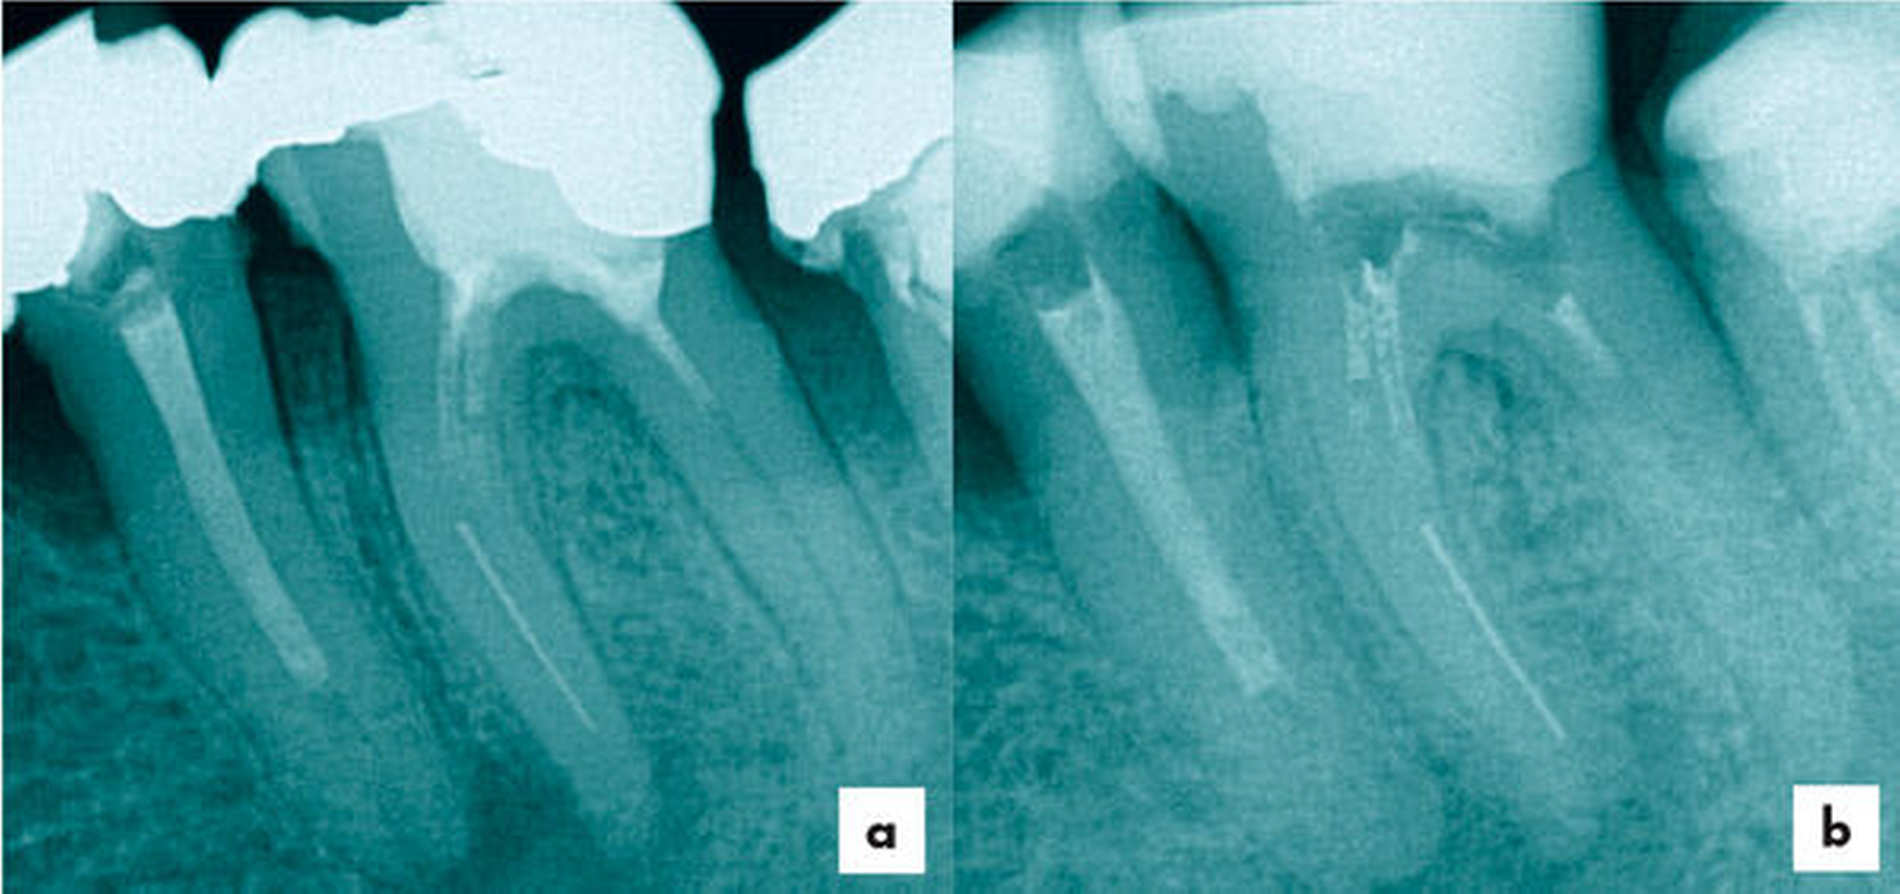

Eine 37-jährige Patientin mit einem frakturierten Nickel-Titan-Instrument in der mesiolingualen Wurzel von Zahn 36 wurde zur Weiterbehandlung überwiesen (Abbildung 6).

Mit einer Reciproc R25 (VDW) wurde zuerst die koronale Wurzelfüllung (Abbildung 7) entfernt, anschließend wurden die Kanaleingänge erweitert. Wie bei Fall 1 wurde zunächst das Fragment circa 3 mm koronal mittels Ultraschalltechnik (VDW Ultra/Endo Chuck) freigelegt und mit der oben beschriebenen Technik entfernt (Abbildung 8).